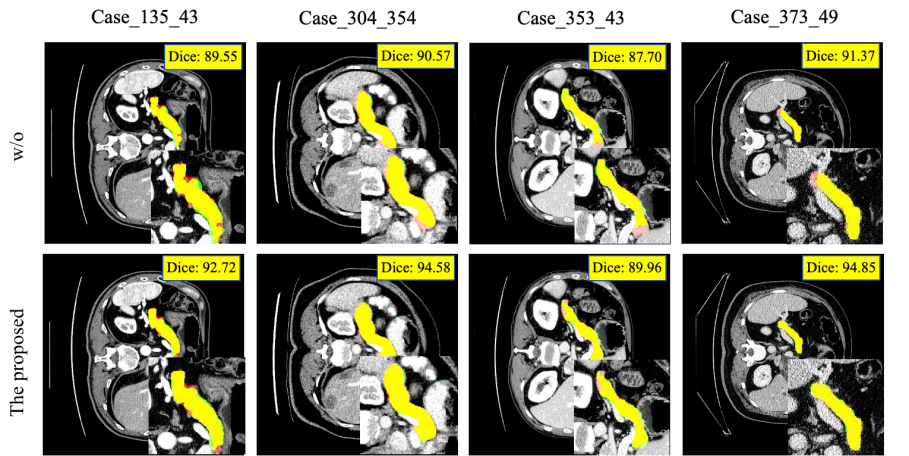

Refer to caption

Figure 4: Comparison of segmentation results on different instances without (first row) and with (second row) the level set evolution. Contours: Red = Gold Standard, Green = Predicted Result.

5.2.1 Five–Fold Cross–Validation

This section provides a comprehensive evaluation of the model generalization by performing five–fold cross–validation on the AbdomenCT-1K dataset. As shown in TABlE 1, a quantitative comparison of all validation sections shows robust performance stability, with the proposed model achieving state-of-the-art performance across all key evaluation metrics including mean, standard deviation, maximum, and minimum. In addition, we can see that in addition to the comprehensive five–fold cross–validation results, we show the five–fold separate results, and we can see that the performance of each fold is advanced and stable. As shown in Fig.4, we can see that the diffusion probability model combined with the level set model significantly improves the performance of the model. Both over–segmentation and under–segmentation of the top of the pancreas of Case_135_43Case\_135\_43 are significantly improved after level set evolution. In the last three groups of instances, there are obvious undersegmentation in the results of the top and bottom of the pancreas in the first row. After the level set evolution, the corresponding results are successfully segmented. Our model can effectively compensate and improve the undersegmentation problem of the diffusion probability model, and alleviate the over–segmentation problem.